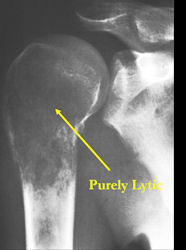

There are 3 radiographic presentations for osteosarcomas, depending upon the amount of osteoid/ossification and calcium deposition:

- Mixed sclerotic and lytic, permeative lesion most common radiographic presentation

- Purely osteoblastic, permeative lesion: dense sclerosis and osteoid production

- Purely lytic, permeative lesion: little osteoid production and/or minimal calcium deposition in osteoid

Conventional osteosarcomas are permeative lesions on plain radiographs (borders of the lesion cannot be clearly delineated)

- Wide zone of transition from lytic/sclerotic areas of tumor to normal bone

- Makes borders of lesion hard to define